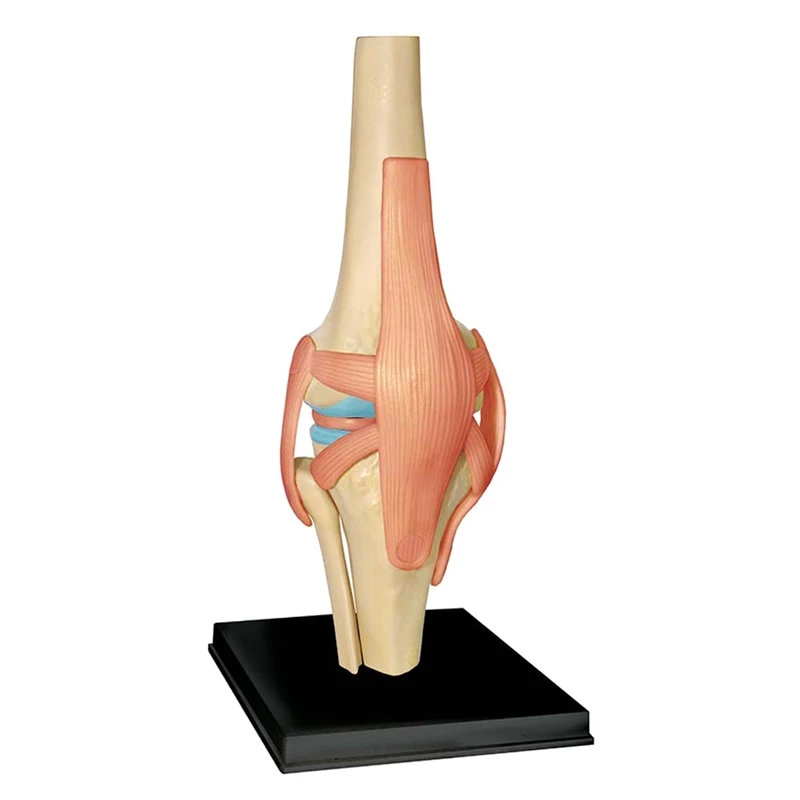

Модель человеческого тела, модель для образования коленных суставов, модель для студентов, обучающая Модель для сборки